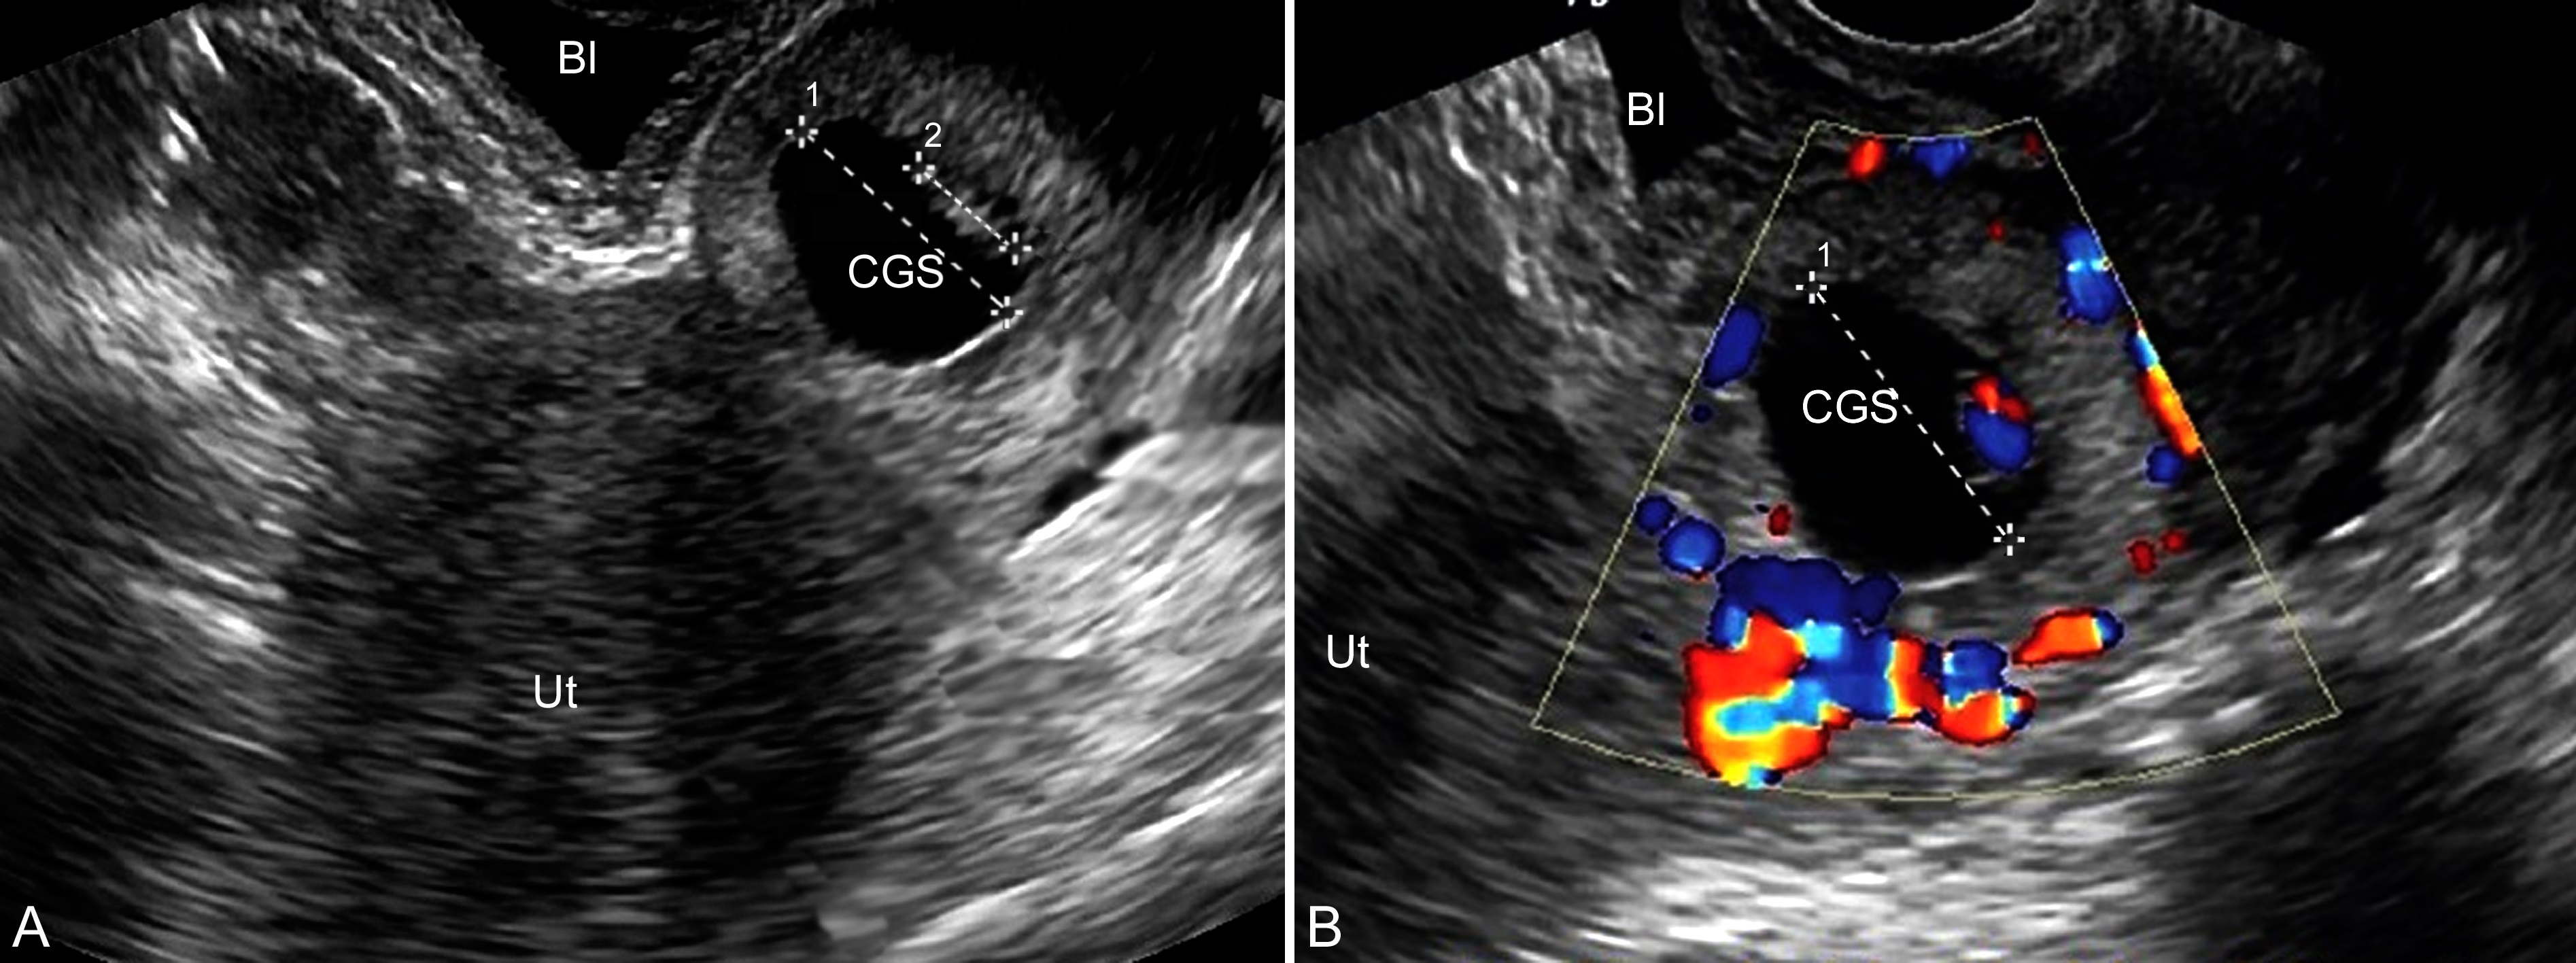

1.超声显像检查 经腹或经阴道的超声显像检查可以发现子宫腔内膜增厚,但无妊娠征象,或可以显示“假孕囊”、宫腔积液等;子宫颈内口关闭,颈管明显扩大,内部可以显示妊娠囊或/和胚胎及其心管搏动(图1A)。多数病人于就诊时已有出血、胚胎已经死亡,超声显像检查仅能在子宫颈管内显示异常的团块状回声,可以呈囊性或混合性,或只显示异常的不均匀团块状回声。要注意经阴道超声显像检查可能诱发阴道流血。

2.超声多普勒检查 彩色多普勒血流显像检查可以在子宫旁显示丰富的血流,子宫颈血流,尤其是孕卵种植位置更为丰富(图1B),呈典型的低阻力高速血流。有作者提出以子宫颈内口旁的子宫动脉与妊娠团块内的血流参数的对比关系来区分子宫腔妊娠和子宫颈妊娠。宫颈团块内的血流速度高于子宫动脉和/或搏动指数(PI)、阻力指数(RI)低于子宫动脉时提示妊娠在子宫颈内口,反之则提示为子宫腔或其他部位妊娠。

图1宫颈妊娠声像图:A:宫颈内显示孕囊(CGS)及B:宫颈处孕囊(CGS)血流丰富